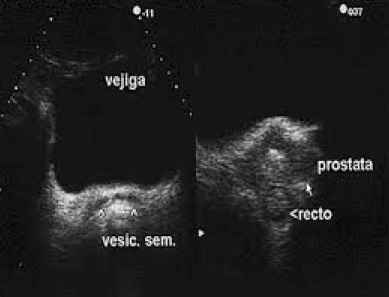

Existen 2 vías de abordaje para la visualización de la próstata: transabdominal y transrectal.

El aspecto ecográfico de una próstata suele ser homogéneo.

La vía transabdominal se suele utilizar para valorar su volumen y el residuo postmiccional.

¿Cómo se ven las vesículas seminales?

Las vesículas seminales son estructuras hipoecogénicas, simétricas, con un grosor anteroposterior de 1 cm.